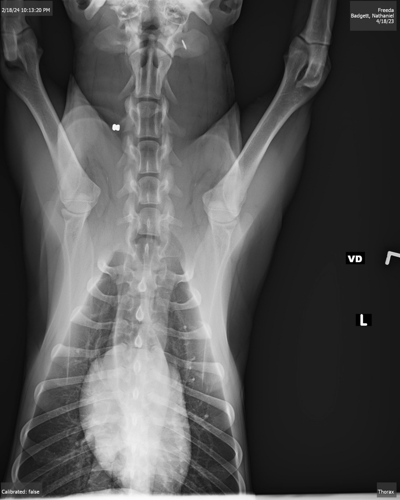

Cpl. Hunter Morrow said when the family "ran outside they seen the blood on the ground. They had rushed the dog to a nearby hospital and had multiple X-rays and the X-rays did reveal what looked like a .22 long rifle bullet in his neck."

A picture of an X-ray image shows the bullet apparently lodged near the vertebrate in the dog's neck area. Morrow said the dog is expected to survive, but has a long road to recovery.

The dog that was poisoned is still recovering. Freeda came home the same night she was shot. Badgett said the bullet is still lodged in her neck, and she is at risk for paralysis.